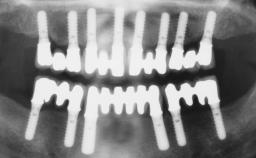

Transition from an “irrational to treat” Maxillary Dentition to a Full-Arch Segmented FDP by Early Loading of Eight Implants Placed Using the Staged Approach

The staged approach permits the transition from an “irrational to treat”dentition to a full arch implant supported restoration without any need to use a removable provisional prosthesis or to apply the immediate-placement and immediate-loading techniques.  A failing dentition is the usual indication for a staged treatment. On the other hand, the dentition should still contain many residual teeth, but with few or none of them being suitable for use as definitive abutments for a full-arch fixed restoration.This situation is usually the result of advanced periodontal disease or of the failure of an extensive fixed prosthesis.

# of Implants 8

Type of Implants One-Piece

Defining Characteristics Fully edentulous upper jaw to be rehabilitated with four or more implants

Modality Fixed hybrid bridge on 5+ implants

Bone Volume Deficient horizontally, allowing simultaneous augumentation